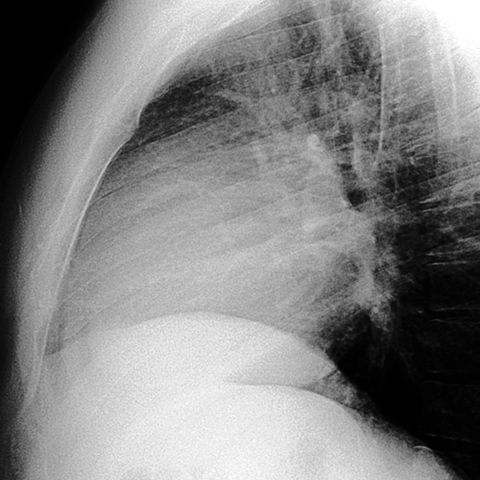

Pericardial Effusion [7 of 8]